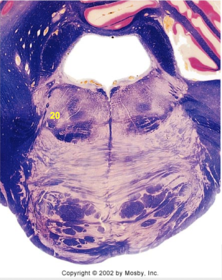

| Nucleus gracilis | |

| Accessory nucleus | |

| Medial longitudinal faciculus | |

| Pyramidal decussation | |

| Medullary pyramids | |

| Anterior spinocerebellar tract | |

| ALS | |

| Posterior spinocerebellar tract | |

| Spinal tract of V | |

| Spinal nucleus of V | |

| Nucleus cuneatus | |

| Fasciculus cuneatus | |

| Fasciculus gracilis | |

| Central canal | |